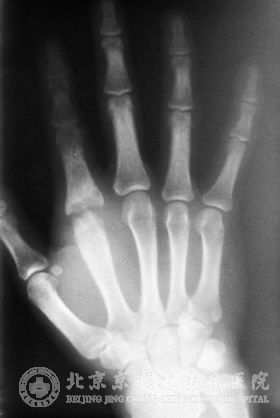

京城皮肤医院的皮肤专家告诉我们,化脓性关节炎是由金黄色葡萄球菌所引发的疾病,有些症状与痛风相类似,但是化脓性关节炎还是有自己的特点:

1.临床上会有化脓病灶或原发感染;

2.好发于髋、膝等关节,全身会伴有寒颤、高热;

3.关节腔穿刺液呈现出脓性渗出液,并进行涂片镜检,我们可以看到金黄色葡萄球菌和革兰阳性葡萄球菌;

4.滑液中查出无尿酸盐结晶;